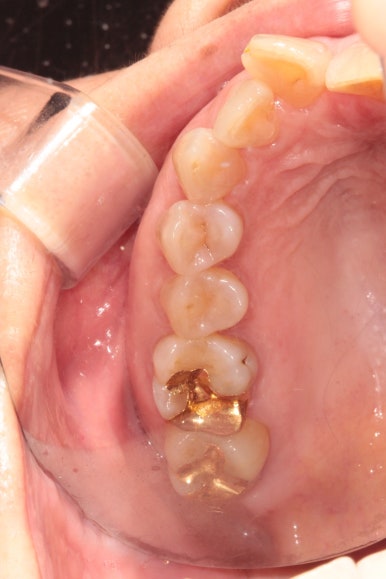

그리고 교합면 사진을 통해 전체적인 진행 상태도 파악할 수 있죠.

씹는면에서 보아도 상당히 가지런히 완성된 것을 보실 수 있습니다.